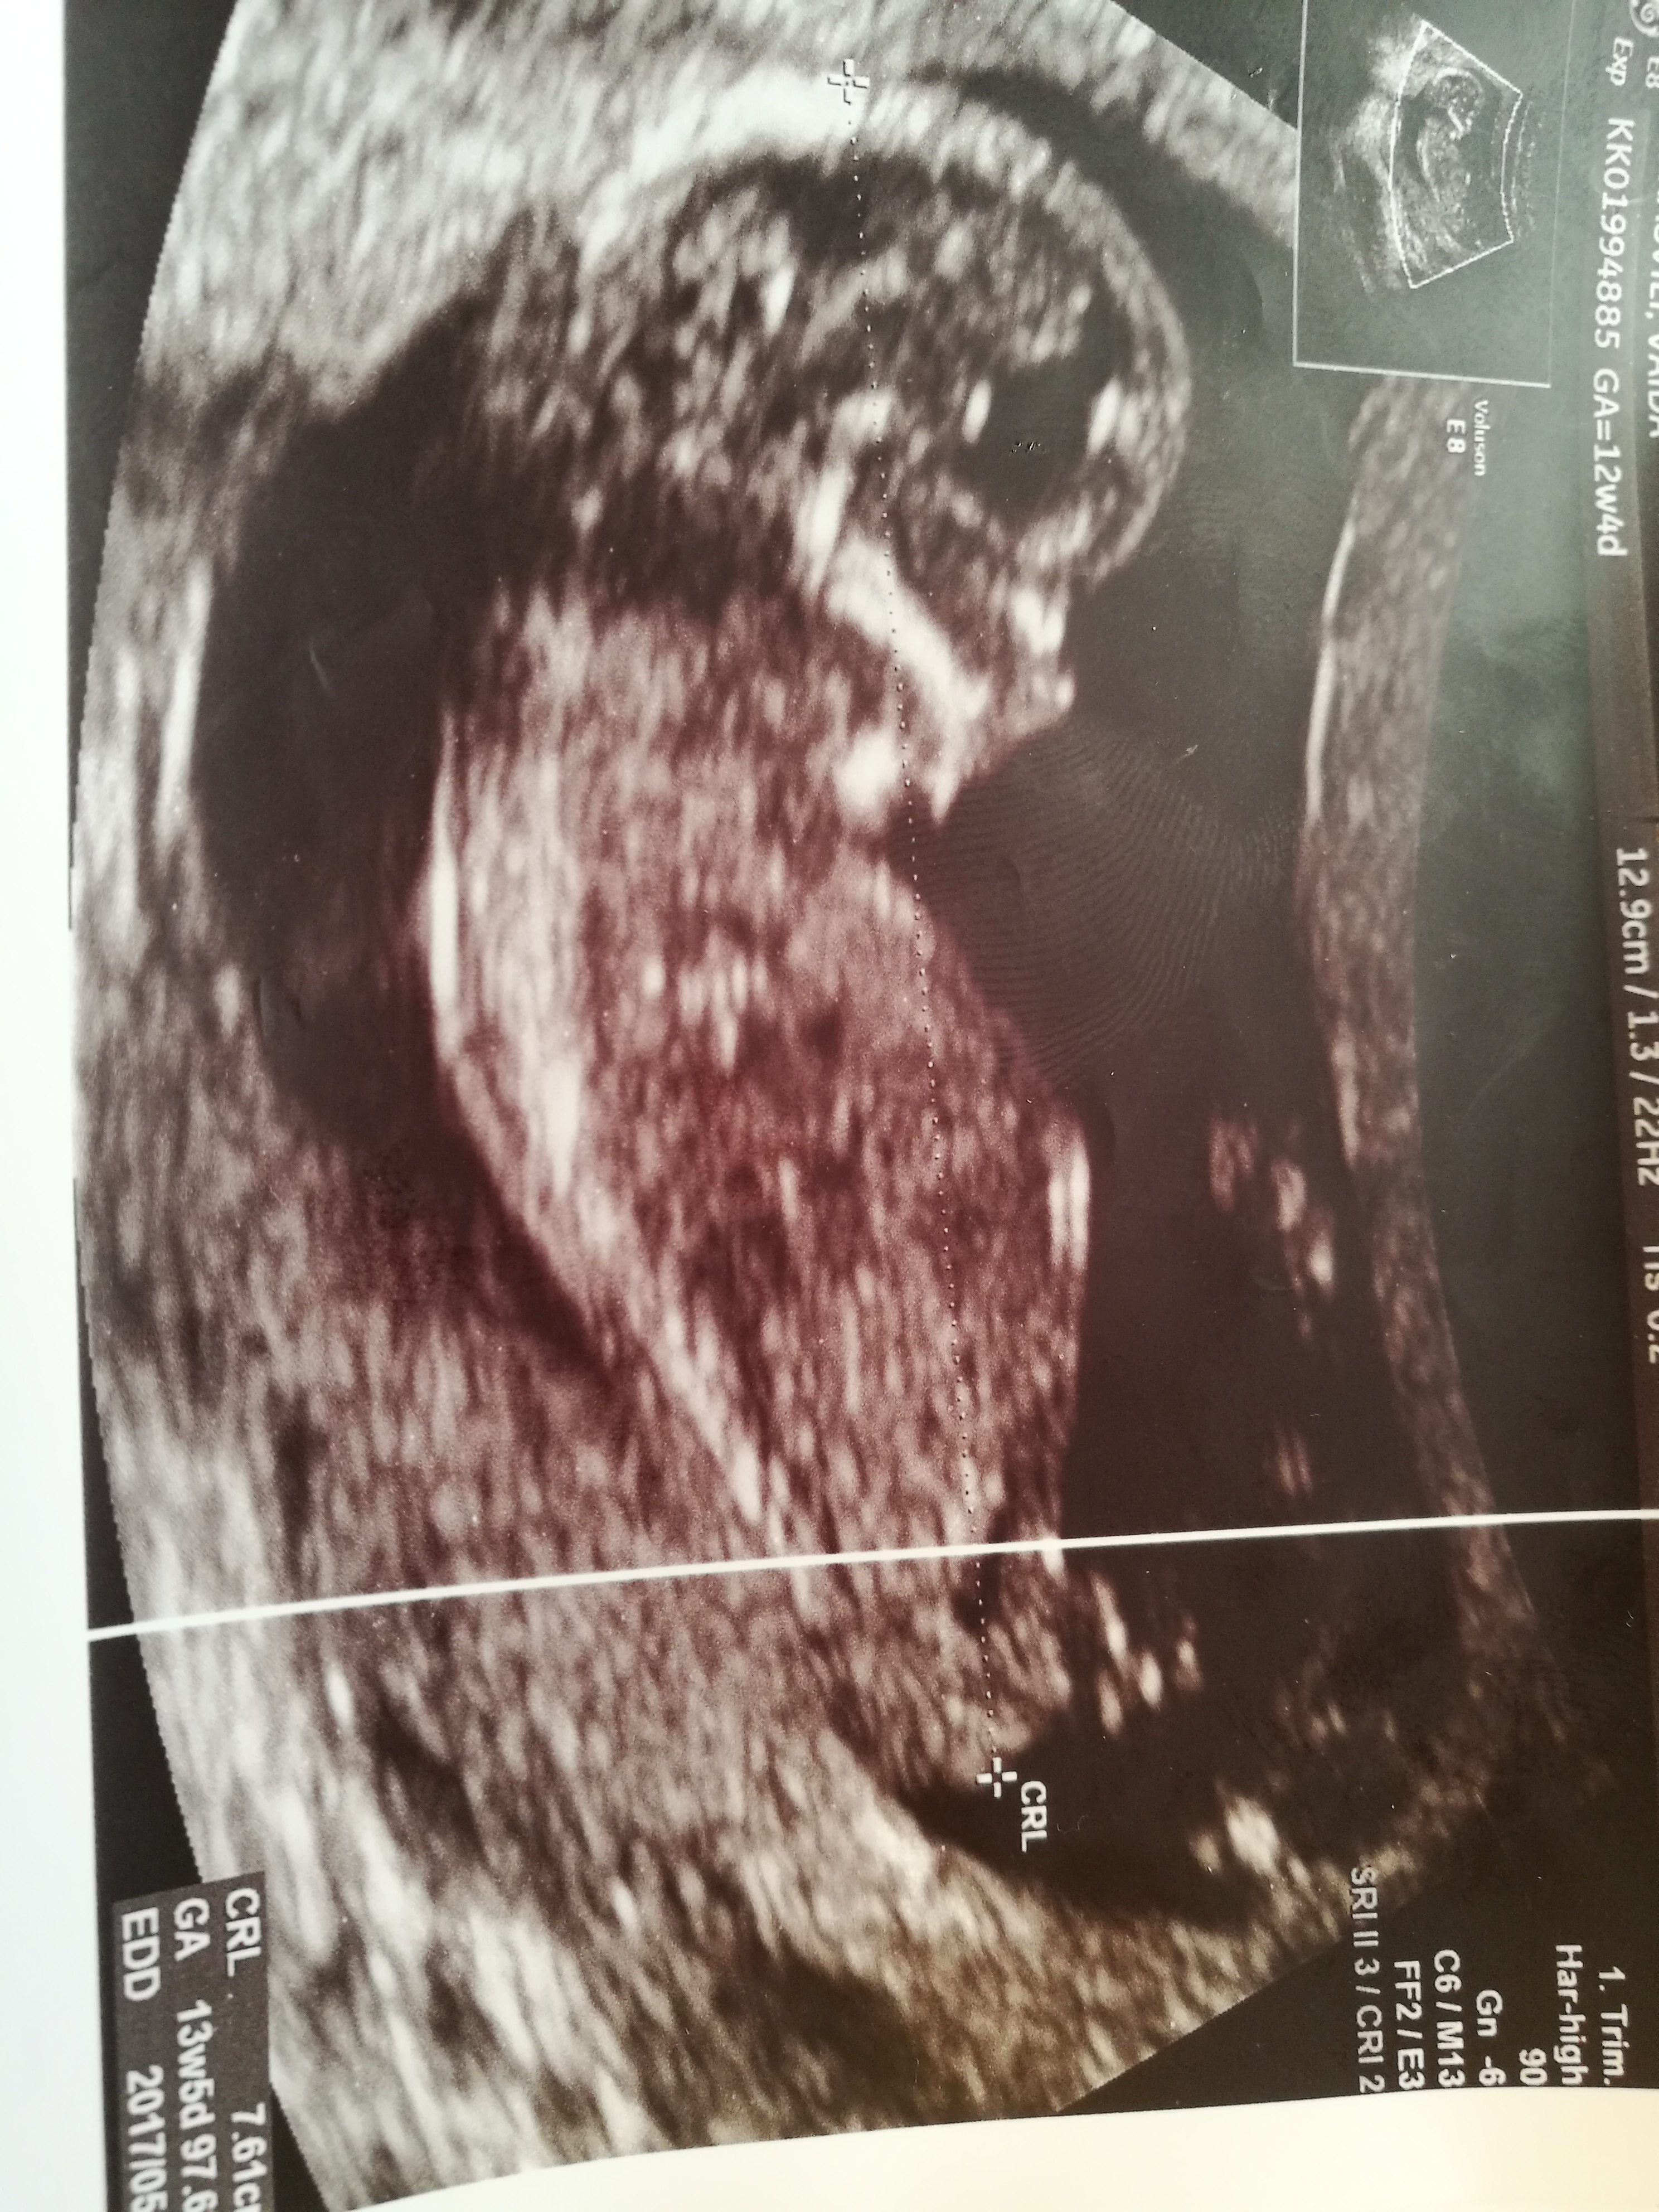

Gender guess? Boy or girl?Attachment 34427Attachment 34428

Tricky to tell as there's lots going on in the nub area; id hazard a guess at boy if what I'm seeing is stacking down there...

Leaning boy